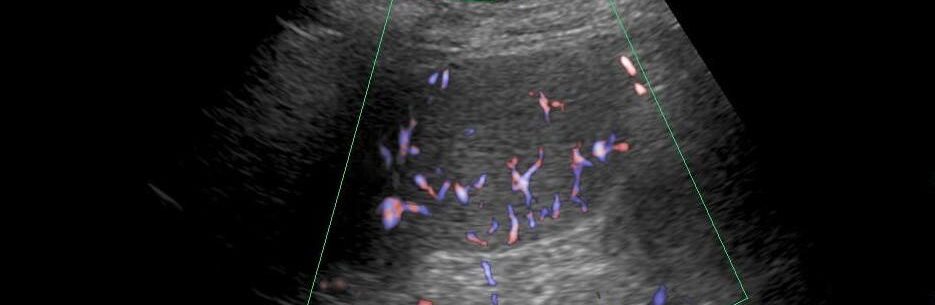

超音波検査所見|等エコー腫瘤とドプラでのバスケットパターン

脾臓と実質エコーが同等の円形腫瘤を認めます。

カラードプラでは

バスケットパターンのようにも見えます。

超音波検査上、脾臓過誤腫は通常、境界明瞭な均一な等エコーまたは低エコーの腫瘤として認められ、パワードプラでは内部血流信号の特異的な「バスケットパターン」が認められることがあり、これは本診断を強く示唆する。